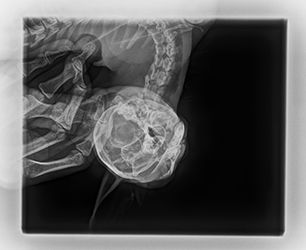

Libušce zvoní telefon, volají z veteriny od pana doktora Herynka v Černicích, že k nim majitelé přivezli tříměsíční koťátko, které neotevře tlamičku. Hledají pro něj pomoc a chtějí vědět, zda se ho ujmeme, jinak by ho museli uspat. Libunka okamžitě volá Lindě. Záměr je takový, že kocourek by měl být v dočasce v Praze a zkusíme, zda by ho odoperovali na Animal Clinic. Lindička akorát veze Medinku do nového domova za Plzeň, takže chlapečka vyzvedne cestou zpět. Leonidase přebírá s tím, že se zvládá sám najíst. Od pana doktora dostáváme zprávu a také rentgeny, které na veterině pořídili.

Leo absolvuje nové CT vyšetření. Je zřejmé, že oproti původní diagnóze (špatně zhojené poškození měkkých tkání), je z nových snímků jasně patrné, že Leo má špatně zhojenou zlomeninu spojení spodní čelisti a podočnicového oblouku na levé straně, což je důvod, proč se mu pusinka opět zavřela. Je nutná operace. Po krátké konzultaci v Nuslích Linda domlouvá, aby Lea odoperovali akutně na Zbraslavi. Dostává zprávu, 3D model i CT snímky do mailu.